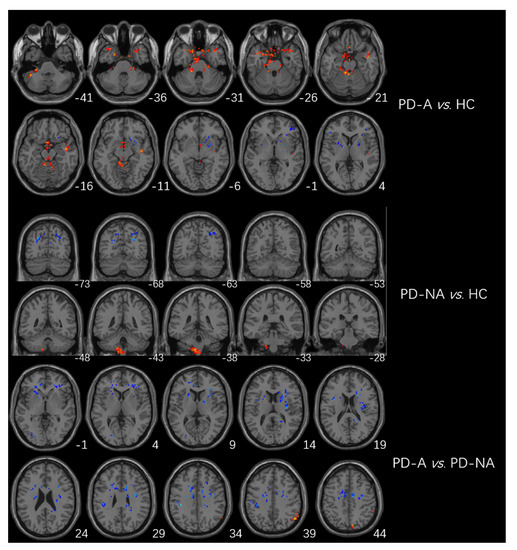

Significant differences in fALFF values among the three groups were mainly located in the left cerebellum, cerebellum posterior lobe, bilateral frontal lobes, bilateral temporal lobes, left occipital lobe, left inferior parietal lobule, right caudate, and right precuneus (Table 2; Figure 1).

Figure 1.

Brain regions with significant differences in fALFF among the three groups (GRF multiple comparison correction, p < 0.01 at the voxel level and p < 0.05 at the cluster level).

The higher fALFF values within the left cerebellum, posterior cerebellum lobe, bilateral temporal lobes, and brainstem, and the lower fALFF values within the bilateral frontal lobes, right basal ganglia areas, and left inferior parietal lobule were identified in PD-A patients compared with HCs (Table 3, Figure 2). Compared with HCs, PD-NA patients showed increased fALFF values in the left cerebellum and cerebellum posterior lobe. In contrast, decreased fALFF values were noted in the right cuneus and left superior parietal lobe (Table 3, Figure 2). When comparing the two PD groups, increased fALFF values of the right precuneus were found in PD-A patients. In contrast, decreased fALFF values were demonstrated in the bilateral frontal lobes, bilateral basal ganglia areas, left inferior parietal lobule, and left occipital lobe (Table 3, Figure 2). The fALFF values in the right precuneus (r = 0.54, p < 0.001) were positively correlated with HAMA scores of PD-A patients (Figure 3). Furthermore, the fALFF values in the left caudate were negatively correlated with HAMA scores of PD-A patients (r = −0.60, p < 0.001) according to Pearson’s correlation analysis (Figure 4).

Figure 2.

Brain regions showing differences in fALFF between groups. The red region represents the brain region with significantly increased fALFF (PD-A > HC, PD-A > PD-NA, and PD-NA > HC), and the blue region represents the brain region with significantly decreased DC (PD-A < HC, PD-A < PD-NA, and PD-NA < HC).